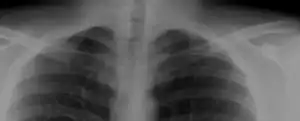

Most cases of cervical ribs are not clinically relevant and do not have symptoms;[6][7] cervical ribs are generally discovered incidentally, most often during x-rays and CT scans.[3][4][5] However, they vary widely in size and shape,[3] and in rare cases, they may cause problems such as contributing to thoracic outlet syndrome,[6] because of pressure on the nerves that may be caused by the presence of the rib.[6][8]

The presence of a cervical rib can cause a form of thoracic outlet syndrome due to compression of the lower trunk of the brachial plexus or subclavian artery.[6] These structures become encroached upon by the cervical rib and scalene muscles.

Compression of the brachial plexus may be identified by weakness of the muscles around the muscles in the hand, near the base of the thumb. Compression of the subclavian artery is often diagnosed by finding a positive Adson's sign on examination, where the radial pulse in the arm is lost during abduction and external rotation of the shoulder.[6] A positive Adson's sign is non-specific for the presence of a cervical rib however, as many individuals without a cervical rib will have a positive test. Compression of the sympathetic chain may cause Horner's syndrome.